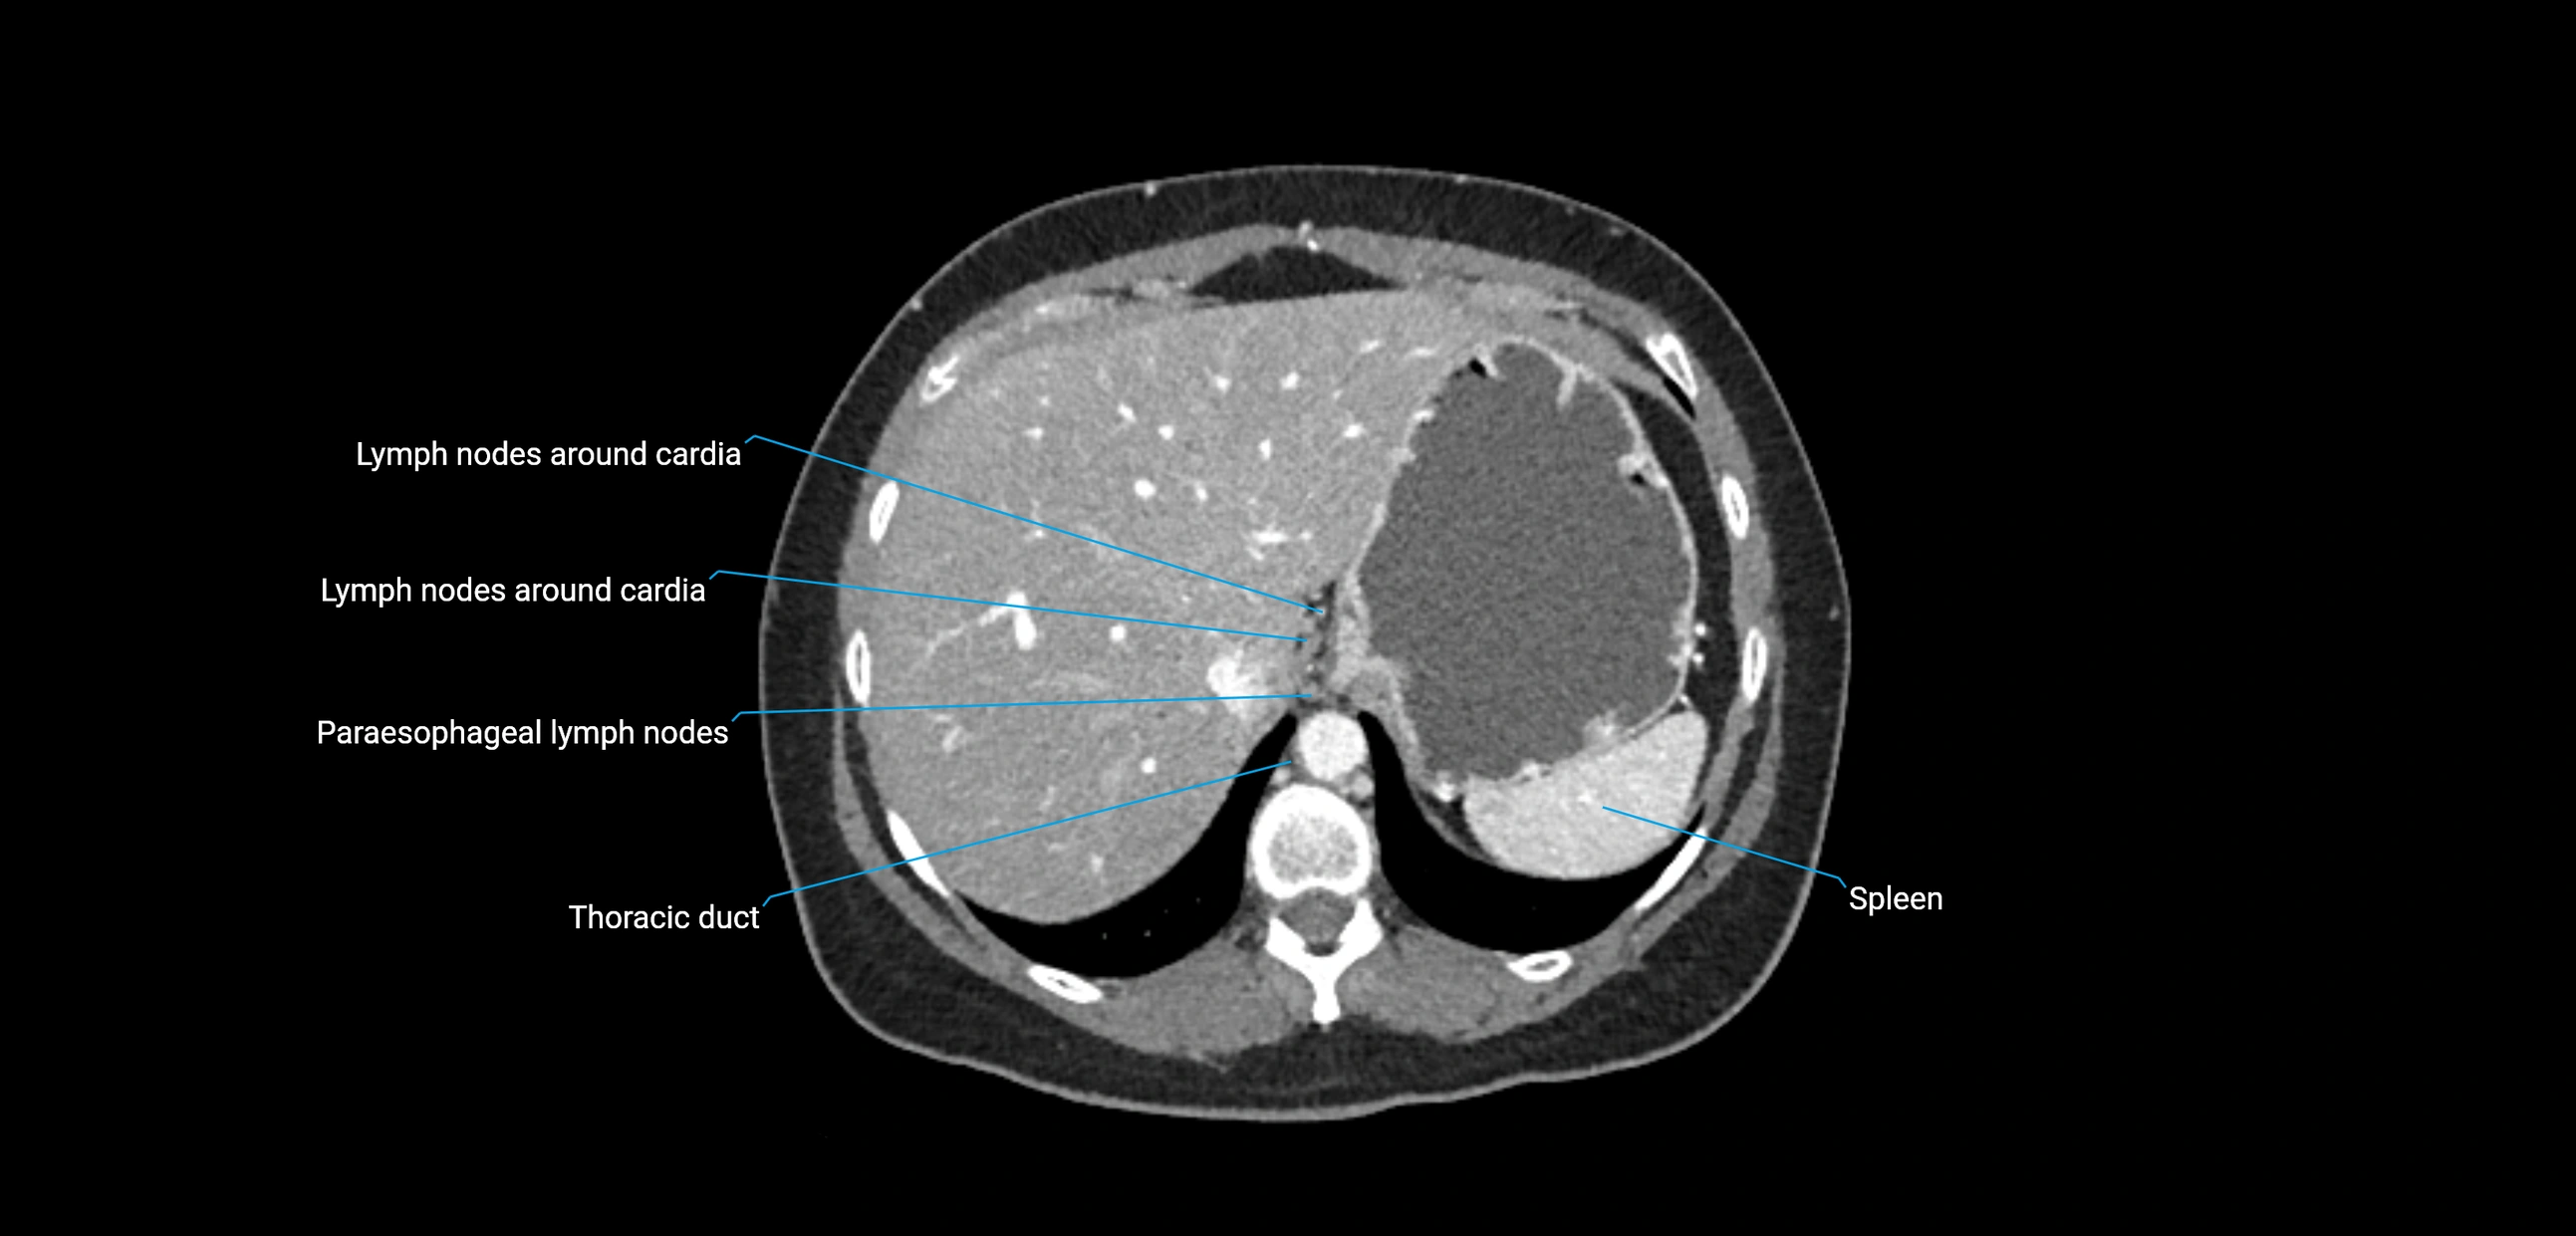

CT Appearance

CT Pre-Contrast:

• Nodes appear as soft-tissue density nodules adjacent to the aorta and IVC

• Calcification may be seen in chronic infections (e.g., tuberculosis)

CT Post-Contrast:

• Normal nodes enhance homogeneously

• Malignant nodes may show heterogeneous enhancement, central necrosis, or conglomerate formation

• Size >1 cm short axis is suspicious, though morphology and distribution are equally important

CT image

image